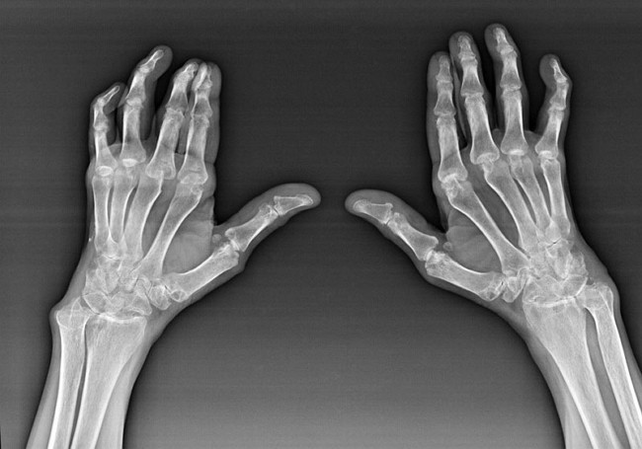

A reumatoid arthritis olyan betegség, amelyben az emberi immunrendszer károsítja a test saját szöveteit. Más szavakkal, a rheumatoid arthritis autoimmun patológia. Ez a betegség szintén szisztémás, mivel sok szövetet érinti (izmok, ízületek, erek stb.) és szervek (Szív, vesék, tüdő stb.) a testben.

Annak ellenére, hogy a rheumatoid arthritis szisztémás betegség, amely nagyobb mértékben az ízületek szenvednek, míg más szövetek és szervek sérülése a háttérben van. Ezzel a betegséggel szinte minden típusú kefe -ízület befolyásolhatja (karfalak, carpalis-útvonalak, Metacarpal-Phalanx, Phalanx ízületek). A lézió általában szimmetrikus (azok. Ugyanazokat az ízületeket érintik) mindkét kezén, duzzanat, fájdalommal a sérült ízületekben. Reggel, az ágyból való emelés során az érintett ízületekben van némi merevség, amely kb. 1 órát tarthat, majd nyom nélkül eltűnhet.

Gyakran a reumás ízületi gyulladással a kefe érintett ízületei közelében (Gyakrabban a zongorfalanx, a Phalanx ízületek) Rheumatoid csomók jelennek meg. Ezek egy lekerekített formáció, amely a bőr alatt helyezkedik el. A kefén ezek a formációk leggyakrabban a hátsó részen merülnek fel. A tapintás során sűrű, inaktív, fájdalommentes. A számuk változhat.